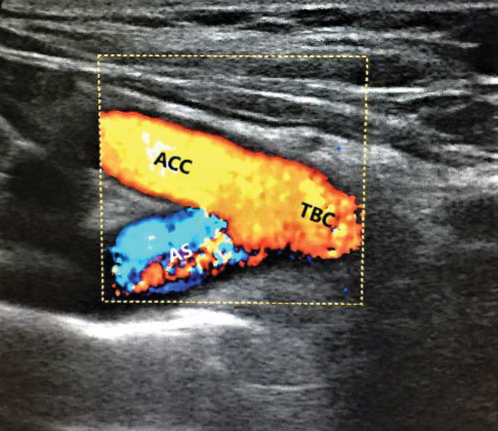

1. Fig. 1. Ultrasound of the vessels of the neck (color duplex scanning). Identification of the Y-sign. ACC - arteria carotis communis dexter, AS - arteria subclavia dexter, TBC - truncus brachiocephalicus. | |